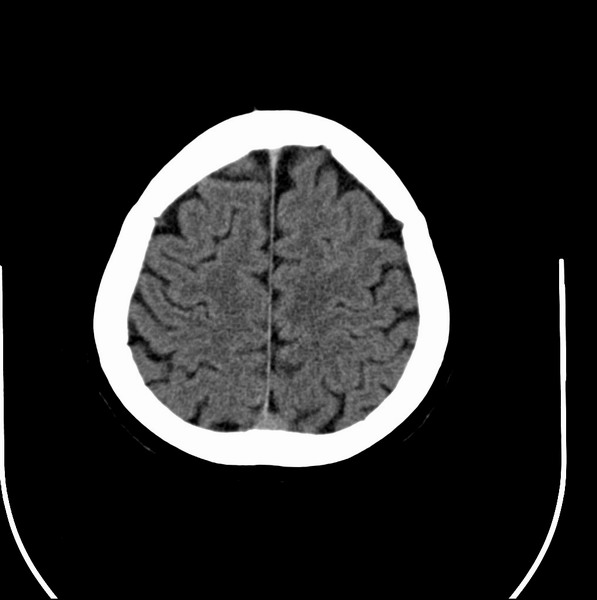

以下是引用余辉在2009-4-25 10:34:00的发言:[br]上矢状窦旁软组织肿块,内有钙化,与上矢状窦边界不清,灶后颅骨内板骨质增生硬化,支持考虑脑膜瘤,建议增强

以下是引用hmyj9在2009-4-25 14:21:00的发言:[br]病灶紧贴颅板处,中心高密度周围见软组织密度,局部颅板有增生,支持脑膜瘤诊断,建议增强。

以下是引用边生丽在2009-4-25 11:55:00的发言:[br][br] [br] 考虑脑膜瘤可能性大;建议行进一步检查。 [br] [br] [br]